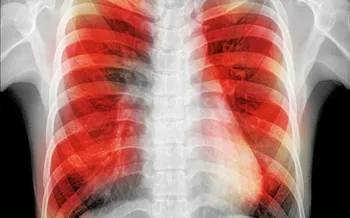

• Study Explains Increased Risk of TB for Smokers

'Clogged-up' immune cells are to blame.

• A ‘Game-Changer’ – Latest TB Research From Trinity

New findings especially useful for drug-resistant forms of the disease